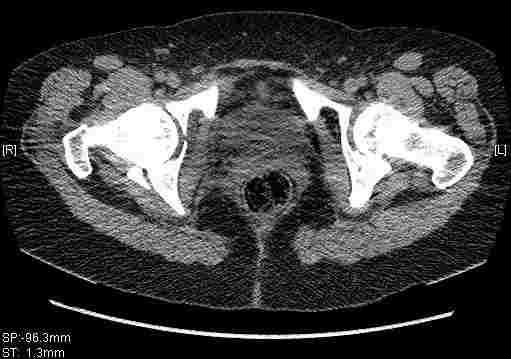

Удалось сегодня вывести пациентку в соседнюю больницу, где есть кт. Срезы сделаны только горизонтальные.